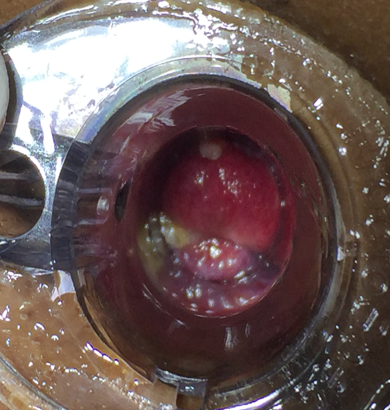

Anoscopy /proctoscopy examination

BARRON’S BANDING

Rubber bands are applied to the pedicle base of internal hemorrhoid so as to cause aseptic necrosis & fall off.

Used for grade 2 & selected cases of grade 3 hemorrhoids.